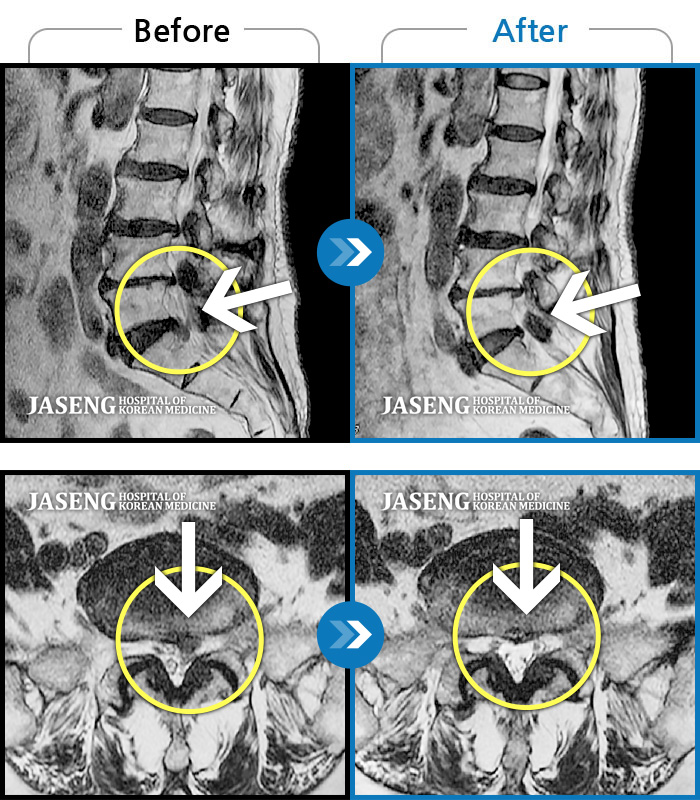

허리디스크

많이 본 사례

인천 · 조남훈 원장

계속 아파서 일을 일주일에 2번밖에 못해요.

촬영시기

2019.11.23 ~ 2023.12.15

2023.12.20

조회수 445